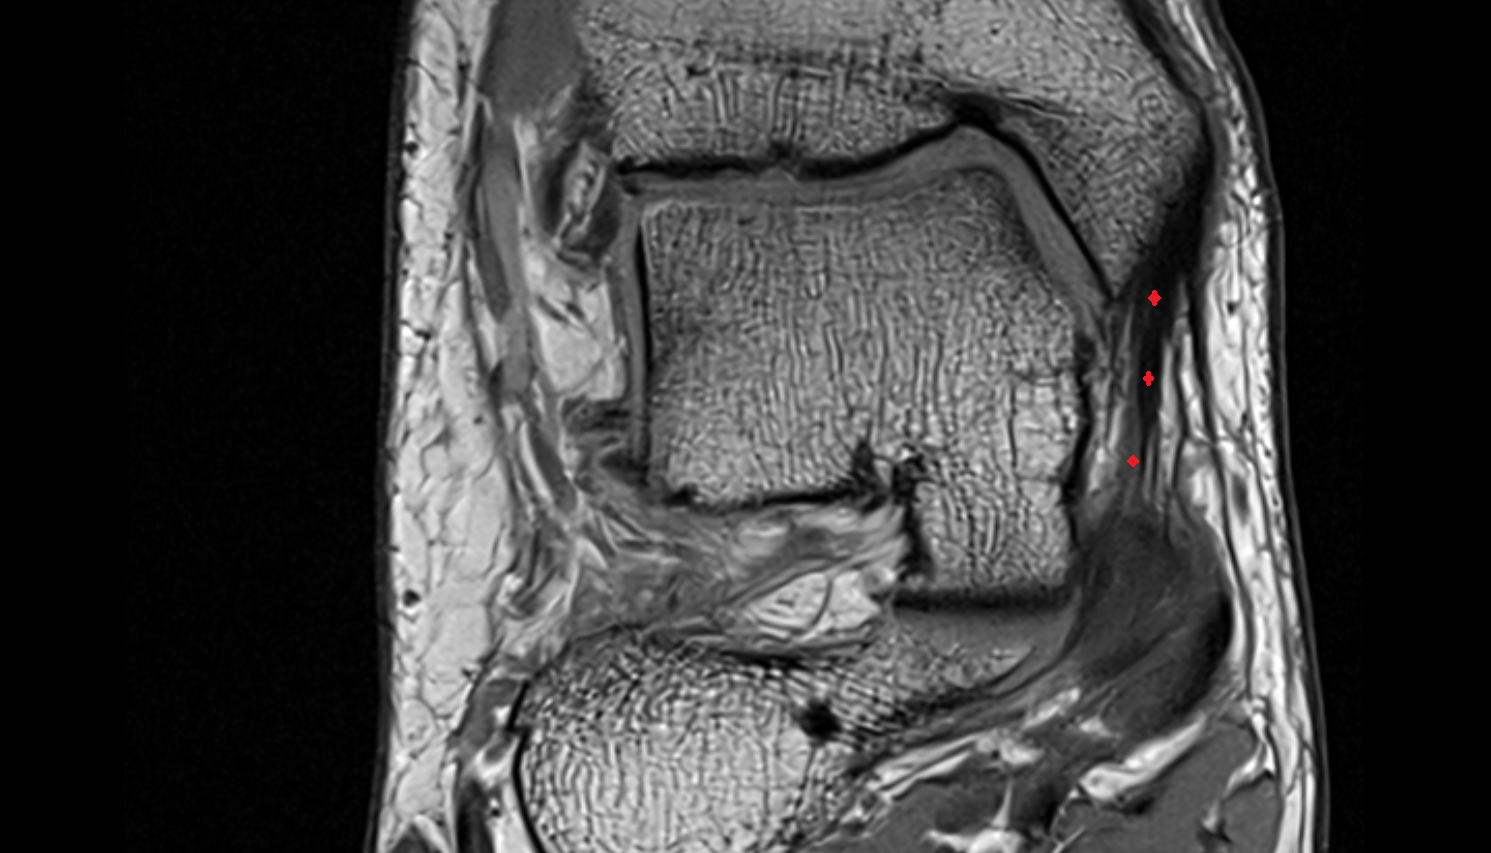

- Temporomandibular joint

- Mandibular condyle

- Mandibular fossa